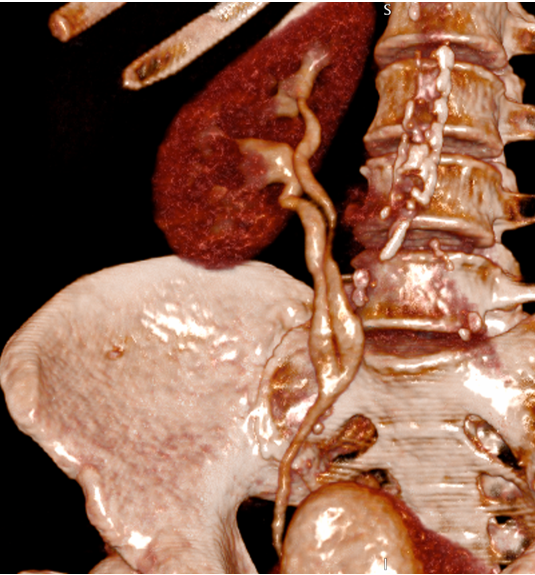

Thank you ESGAR for the Magna Cum Laude award of this #Esgar2023. This award is not only mine but also from my colleagues Dra.Canales, Dra. Garcia Latorre and nicolas almeida and great collaboration of Gopal Punjabi